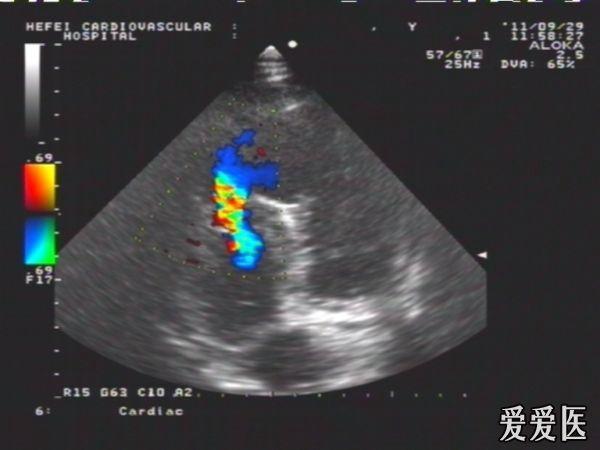

陈旧性前壁心梗继发肌部室间隔缺损典型病例

患者,女性,66岁,活动后心慌,胸闷2年,血压135/70mmHg,HR:78次/分。